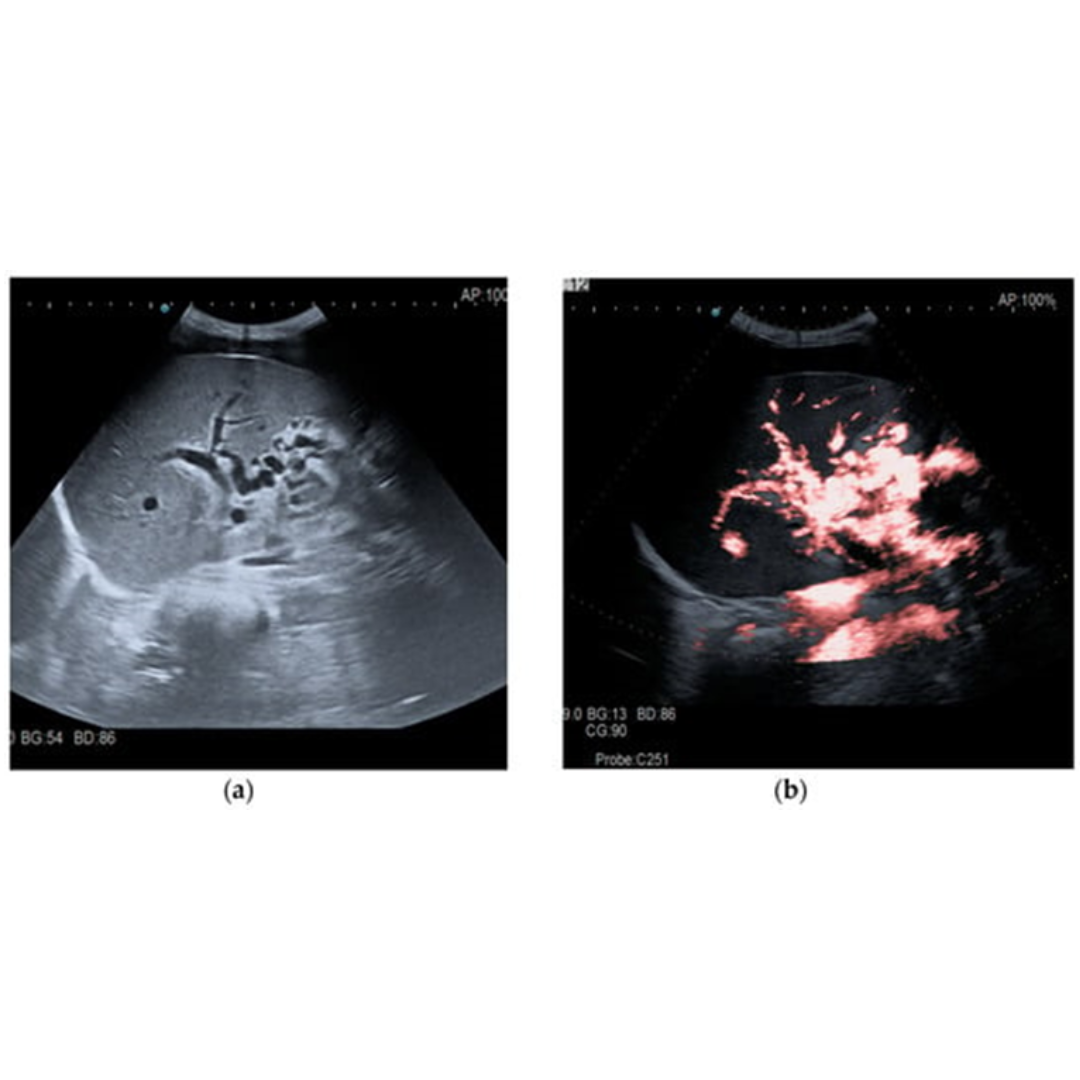

Cavernomatosis Portal

Es una enfermedad poco frecuente causada por trombosis en la vena porta que puede darse por invasión tumoral (hepatocarcinoma), por cirrosis avanzada donde el flujo hepático se ve severamente disminuido hasta trombosarse.

En estos casos se desarrolla una circulación colateral alrededor de una porta con calibre reducido y tromobosada, pudiéndose ver a nivel intra como extrahepático (figura 17 y 18 ).

Figura 17: Transformación portal cavernosa, se observan en modo B múltiples vasos serpiginosas libres de eco que reemplazan a la vena porta en hilio hepático, viéndose presencia de flujo venoso dentro de los cavernosas. (5)

Figura 18: Ramas venosas sinuosas en hilio hepático, con porta trombosada. Doppler color identifica flujo dentro de los vasos.